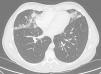

Se solicitó radiografía de tórax posteroanterior y lateral y posteriormente tomografía computarizada (TC) de tórax, que mostró la presencia de nódulos irregulares (acinares), e infiltrados alveolares en lóbulo medio, língula y lóbulos inferiores, de distribución perilinfática y subpleural (fig. 1). Las pruebas de función pulmonar resultaron normales, con FVC 4.830ml (97%) FEV1 3.870ml (93%) FEV1/FVC 80% con DLCO 94%, KCO 94% y VA 97%. Se realizó analítica sanguínea completa y fibrobroncoscopia con toma de biopsia transbronquial con criosonda.

Los hallazgos radiológicos más comunes son opacidades nodulares bilaterales, generalmente menores de 3mm, aunque se han descrito casos de más de 12mm, con distribución centrilobulillar o peribronquiolar. Podemos ver áreas de vidrio deslustrado parcheadas bilaterales de distribución no segmentaria8.